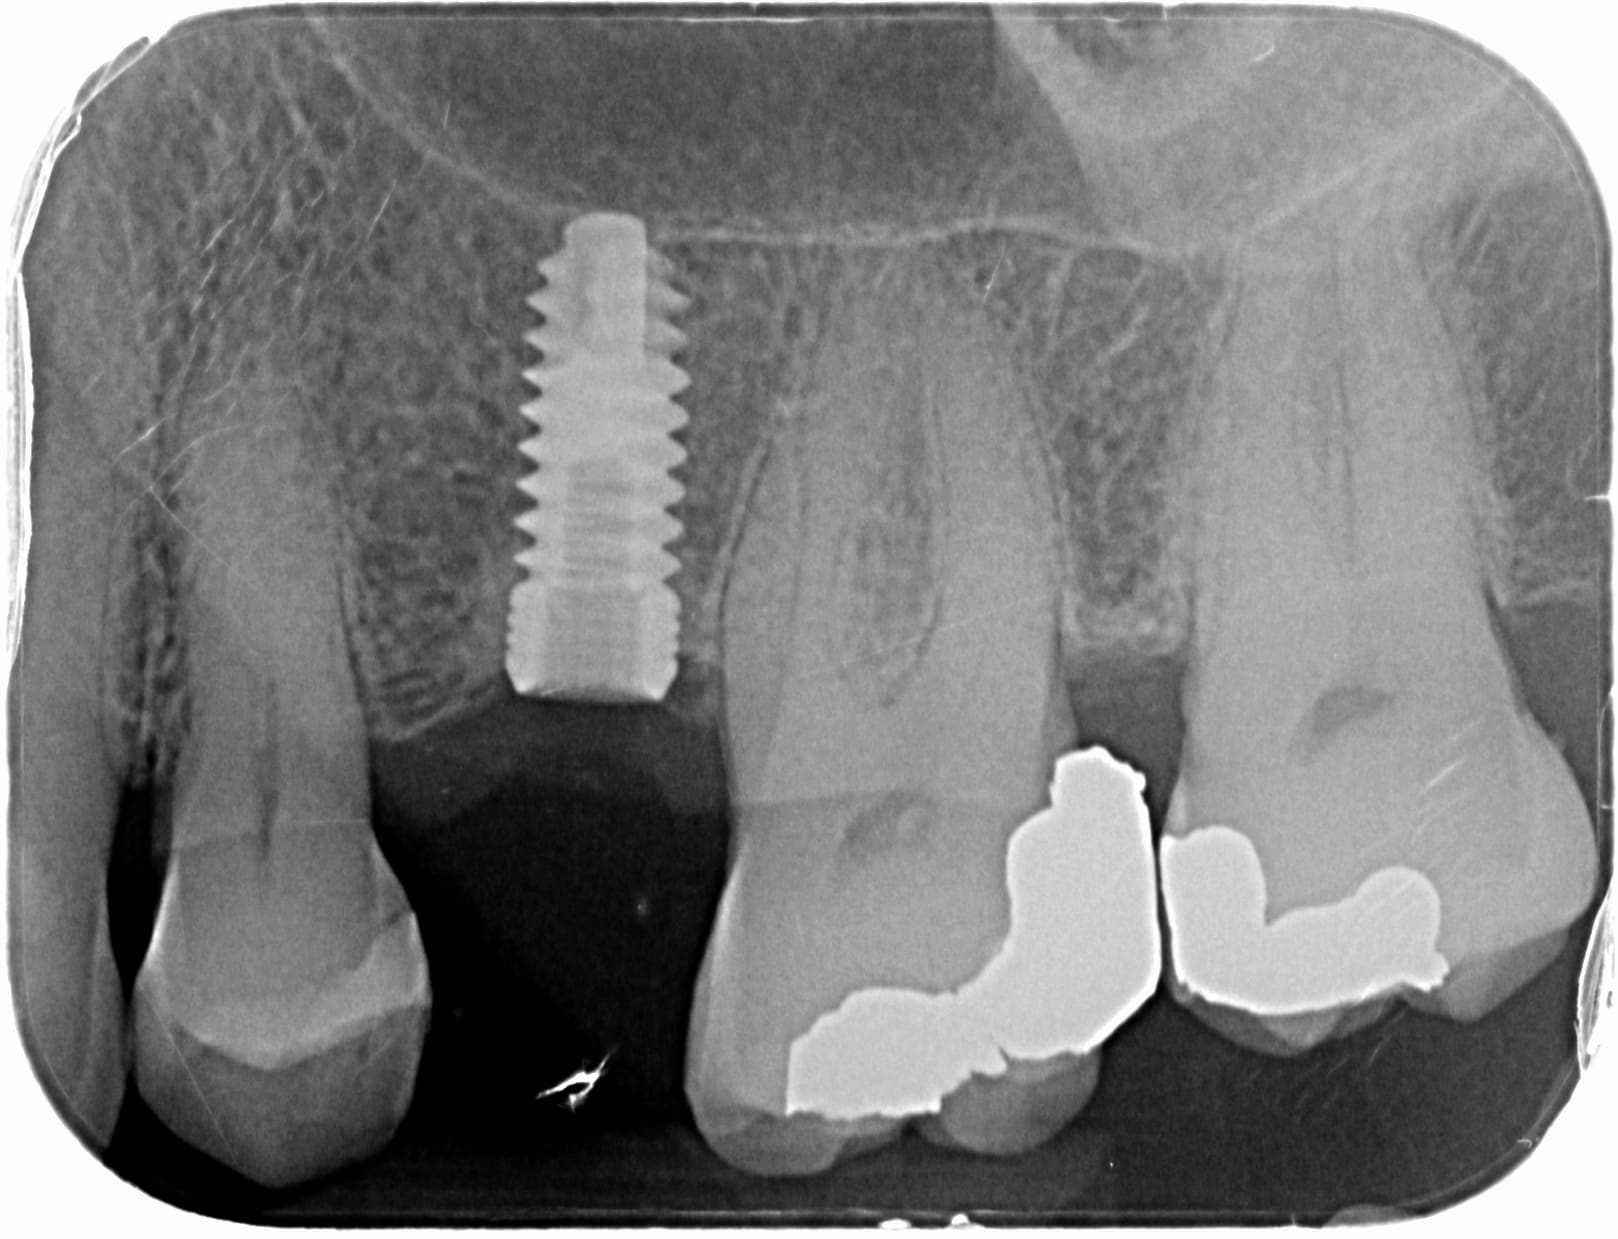

connectique type Zimmer (cone 90° + hexagone interne)

3 rainures au col

filet en v (l'image 3D de l'implant n'est pas complétement de profil donc c'est trompeur)

goujures a l'apex quasi identiques

ca semble concordé

C'est du ADIN Swell, avec un Ø d'au moins 4.2mm.

Mais effectivement connectique type ZIMMER.

ADIN swell Ø4,2